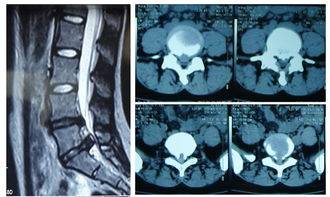

1、巨大型的椎间盘突出。

2、椎间盘突出后髓核脱垂到椎管。